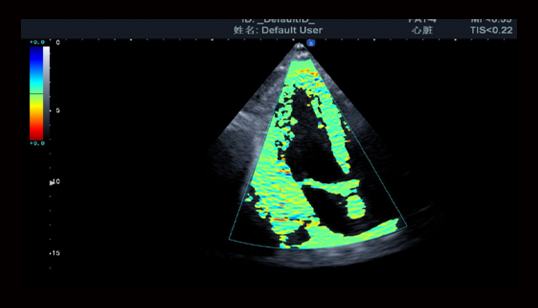

Heart imaging: 心脏成像

高清心脏M型成像

• 对于外形或位置异常的心脏,都能保持M型线与解剖结构垂直。三线M型在同一个心动周期内准确获得心脏组织数据。

TDI组织多普勒成像

• 用于评估心肌活动的方向和时间,显示血管壁运动和心脏组织运动速度

SRI应变率成像

• 通过对图像进行彩色编码,可用于评价心室整体和局部功能,大大增强了心脏检测的临床应用。